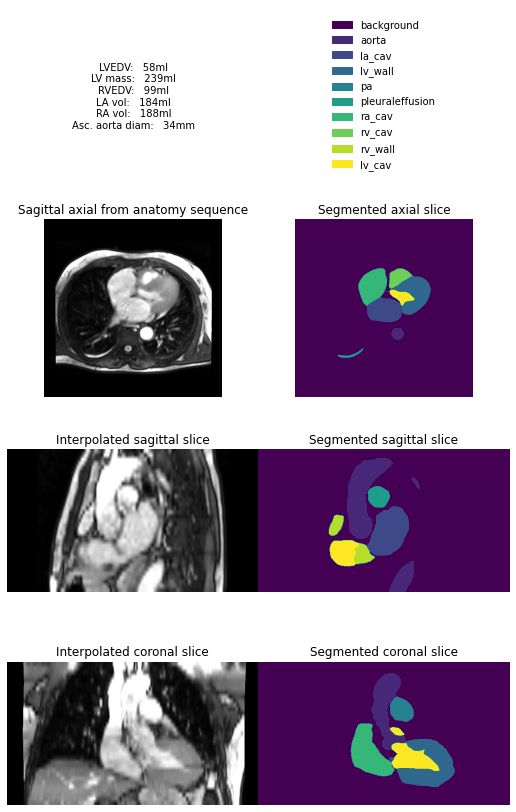

Here we use a neural network to analyse and segment each slice of these images, before combining these slices into a 3D model. This 3D model is then used to estimate common cardiac measurements made by expert humans. The hope is we can get good estimates of these measures right at the start of the scan, so any unexpected findings can be flagged up early.